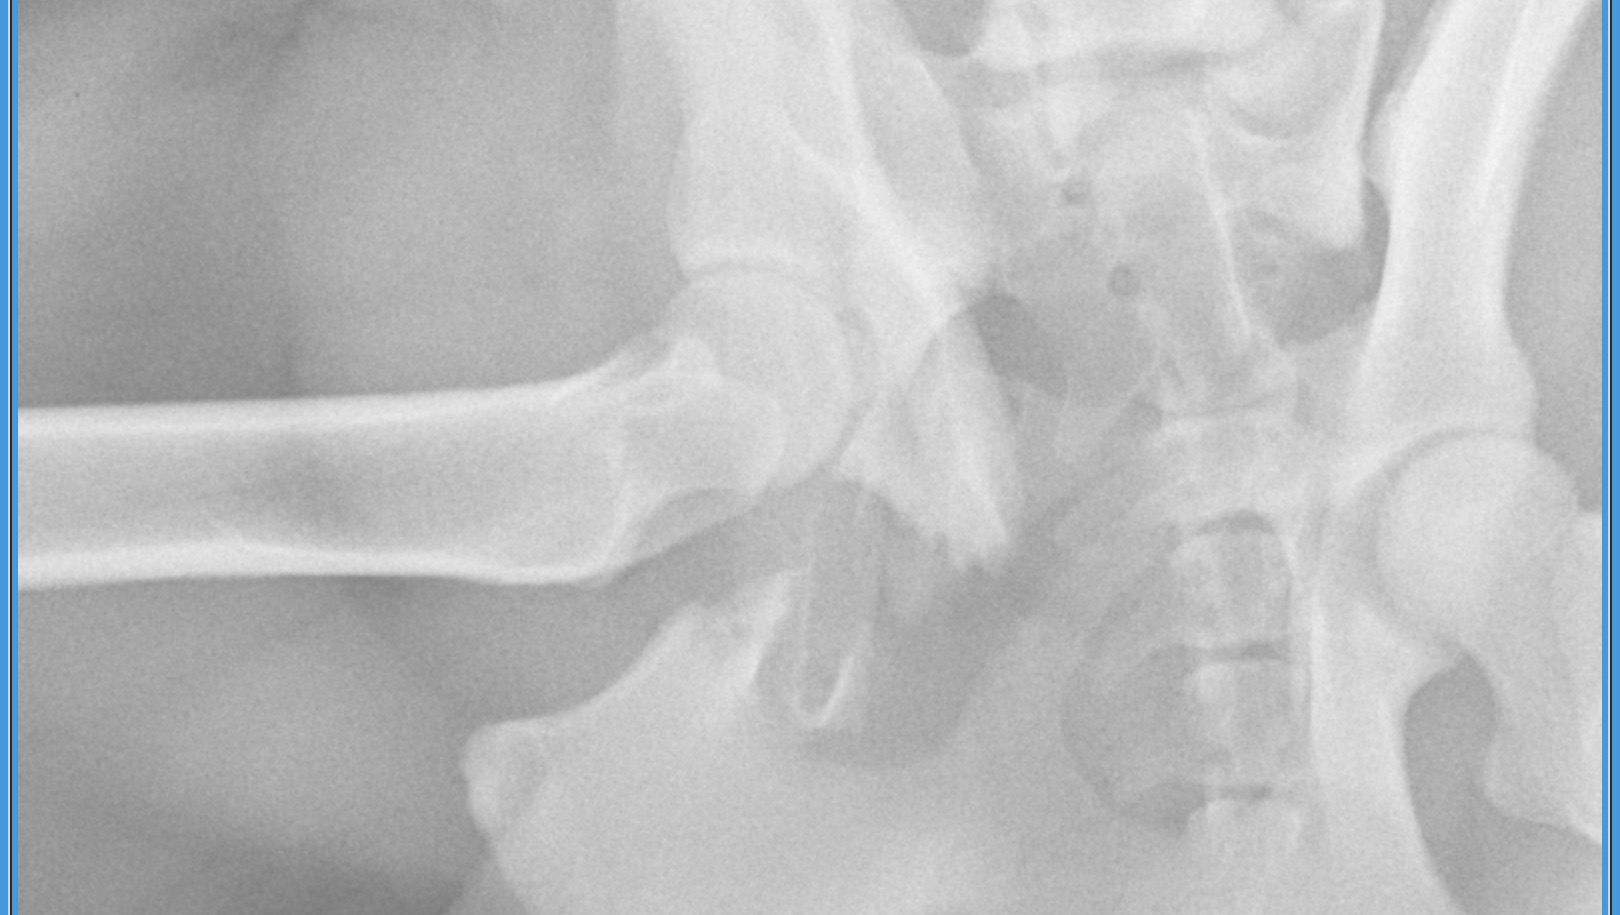

This is our boy Ziggy. Sadly, he somehow got out of our yard earlier today and was hit by a car. We rushed him to Fetch Animal Hospital in Greenville. Once he was stable, they were able to get x-rays. X-rays show bilateral hip fractures. Significant fractures of the right hip. This is going to require surgery to repair. His surgery will be scheduled out until the end of the month. So, in the meantime, we would bring him home with pain meds to keep him comfortable until his surgery date. He will need to be crated and can only use the restroom with assistance from us using a sling to help him. The estimated cost of his surgery is 6500. We have paid down 1400 today just for his office visit and x-rays. Of course we know with Christmas time right around the corner., funds are tight. Same goes for us, so we completely understand! We also don’t want to even think about losing him! Any and everything will be appreciated, even a prayer! We are on a waitlist, so we